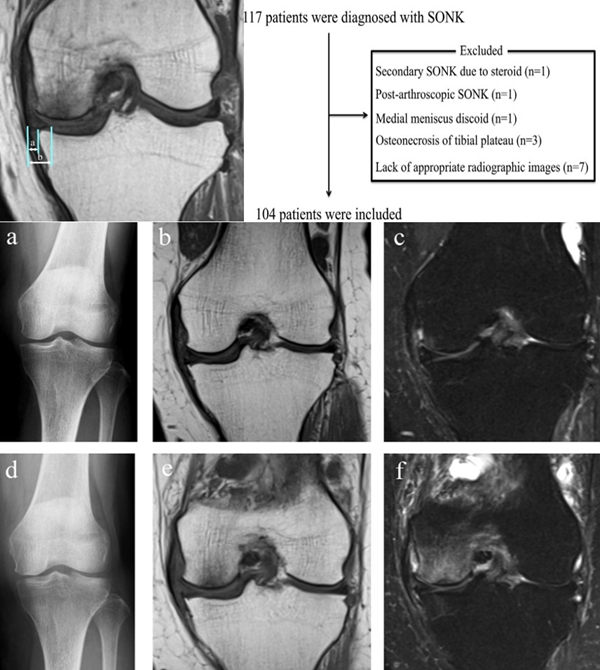

膝关节自发性骨坏死(spontaneous osteonecrosis of the knee,SONK)是指发生于股骨内侧髁负重面深层、原因不明的局部骨坏死,也可发生于股骨外侧髁或胫骨平台,在1968年由Ahlback等首先描述。

病理显示软骨下不完全骨折或局灶性软骨下骨坏死

影像学分及期

X线+MRI:通过测量正位X线片和MRI判断坏死区域的大小。

目前SONK诊断最常用的分期方法是1979年Koshino提出的分期法。Koshino分期基于临床和影像学的结果,将SONK分为四个阶段:

Ⅰ期:患者有膝关节症状,但影像学正常;

Ⅱ期:X线显示负重区变平,软骨下信号升高,周围有骨硬化;

Ⅲ期:受影响区域扩大和软骨下塌陷;

Ⅳ期:病变周围骨硬化和髁突周围骨赘形成的退行性阶段。